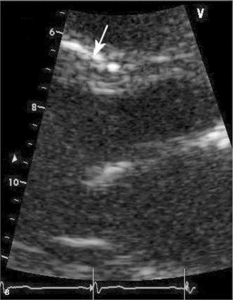

Głównym mechanizmem patogenetycznym twardziny układowej jest zwiększona produkcja aminopropeptydu kolagenu typu III, w następstwie czego dochodzi do włóknienia tkanek (ryc. 1). Zwiększenie sztywności naczyń koreluje z zaawansowaniem choroby [3-5] i może prowadzić do ciężkiego powikłania, jakim jest tętnicze nadciśnienie płucne (ryc. 2, 3) [6].